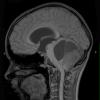

NEOPLASMS (GLIAL)

Astrocytoma, pilocytic - Microscopic (12)